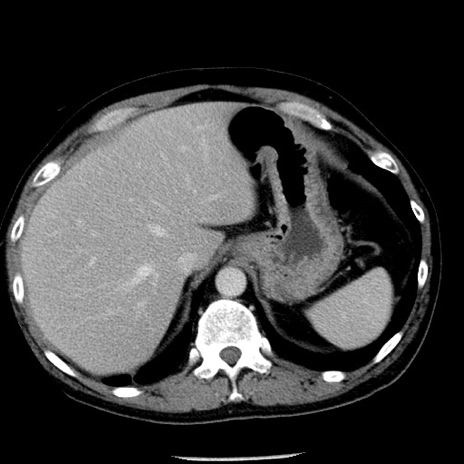

冠状断像

【症例】40歳代男性

【現病歴】2日前から胃痛あり。徐々に周期的な激痛に変化した。本日になっても激痛があるため受診。

【身体所見】意識清明、BT 38-39℃台あり、腹部:膨満、やや硬、右下腹部に圧痛あり。

【データ】WBC 8500、CRP 23.26